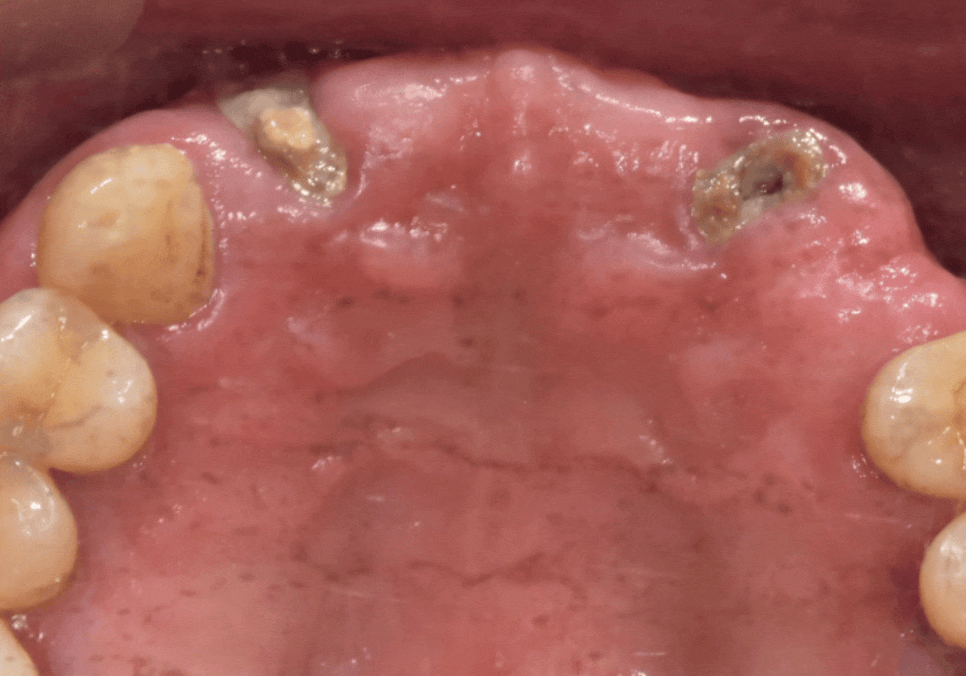

브릿지를 지탱하던 치아 2개(#12, #22)가

잇몸 안에서 완전히 부러져

뿌리만 간신히 남아있는 상태였습니다.

지금 남아있는 뿌리는 단 두 개인데,

이 약해진 기둥 두 개가

다섯 개의 치아(#12, 11, 21, 22, 23)가 받는

엄청난 하중을 전부 견뎌내기에는

사실상 한계가 있었습니다.